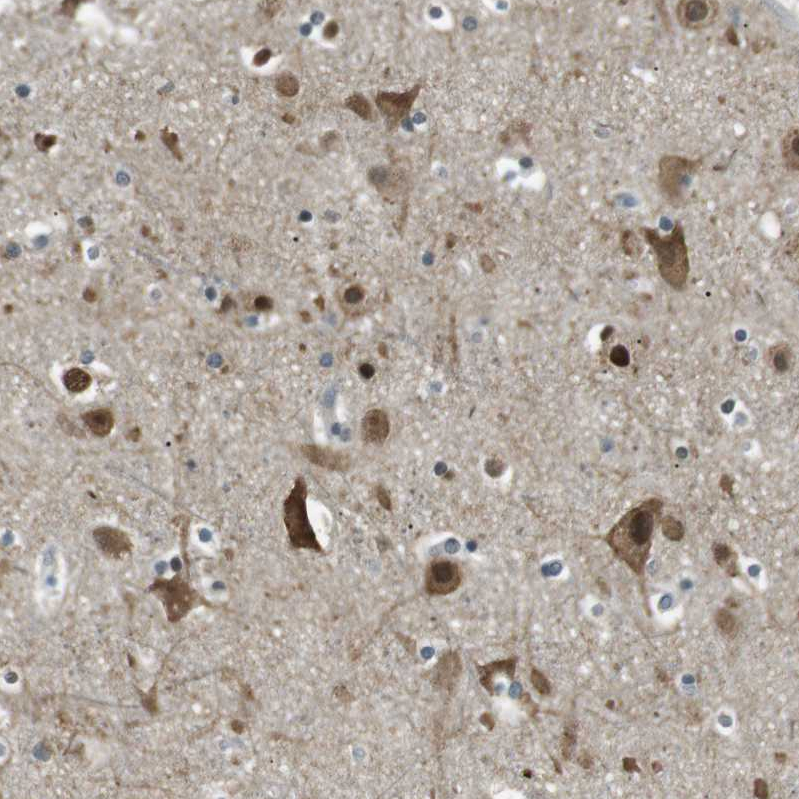

Immunohistochemical staining of human cerebral cortex shows moderate membranous-cytoplasmic positivity in neuronal cells in addition to moderate nucleus positivity.